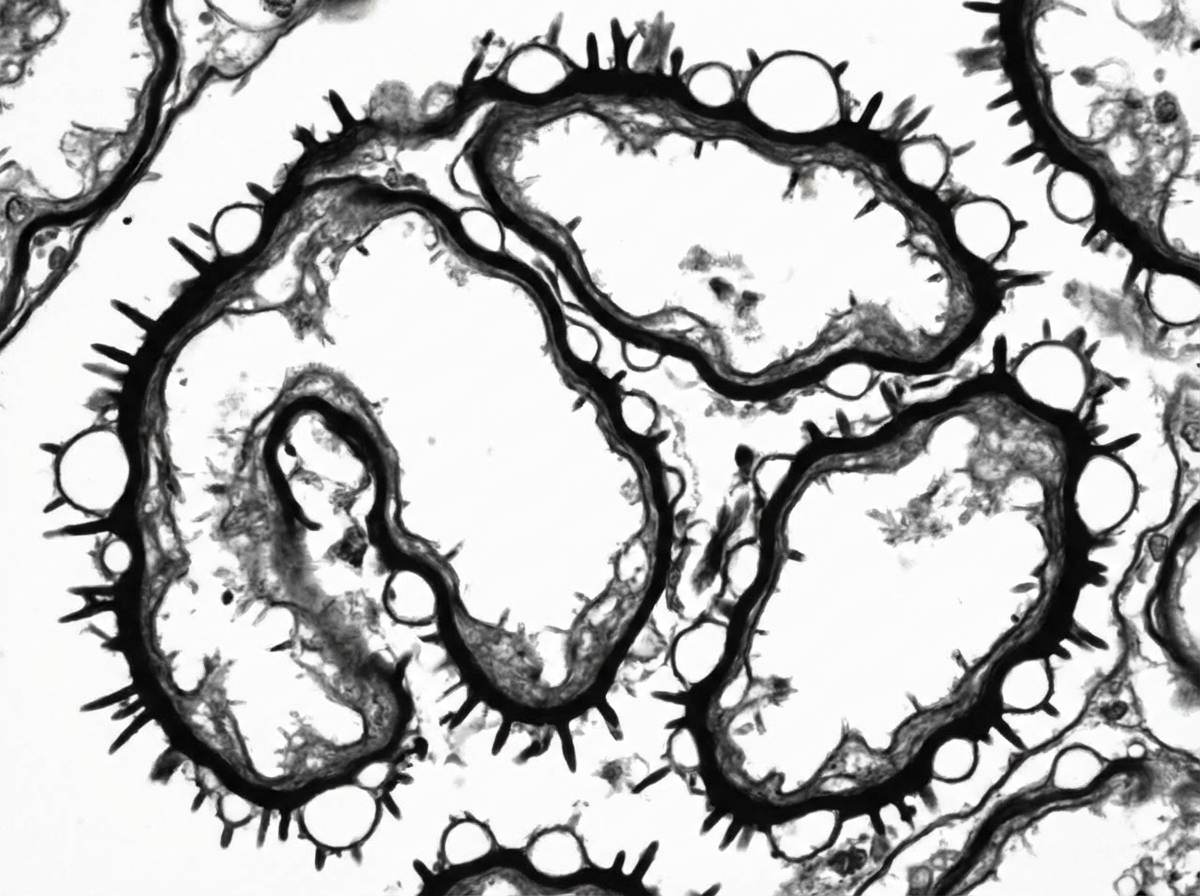

Explanation: ### Explanation **Membranous Nephropathy (MN)** is characterized by the accumulation of immune complexes in the **subepithelial** space (between the podocytes and the GBM) [1], [2]. On Electron Microscopy (EM), these deposits appear as electron-dense masses [2]. Over time, the GBM reacts by growing new basement membrane material around these deposits to incorporate them, creating a **"Spike and Dome"** appearance [1], [2]. As these "spikes" fuse over the deposits, the GBM appears thickened and **split/lamellated**, which is a hallmark of the disease. #### Analysis of Incorrect Options: * **A. RPGN:** Characterized by the formation of **crescents** (proliferation of parietal epithelial cells and monocytes) in Bowman’s space. EM findings vary depending on the underlying cause (e.g., linear IgG in Anti-GBM disease), but it does not show the classic subepithelial splitting seen in MN. * **C. FSGS:** The primary pathology is the **effacement of podocyte foot processes** and segmental sclerosis (hyalinosis) of the capillary loops. There are typically no immune complex deposits. * **D. Minimal Change Disease:** Shows **diffuse effacement of podocyte foot processes** on EM. The GBM appears structurally normal, and there are no electron-dense deposits. #### High-Yield Pearls for NEET-PG: * **Light Microscopy (MN):** Diffuse thickening of the capillary wall; Silver stain (Jones) highlights the "spikes" [2]. * **Immunofluorescence (MN):** Granular IgG and C3 along the GBM [2]. * **Primary MN Marker:** Antibodies against **Phospholipase A2 Receptor (PLA2R)** are found in ~70% of cases. * **Secondary Causes:** Associated with SLE (Class V), Hepatitis B/C, NSAIDs, and occult solid tumors (Carcinoma of lung/colon). * **Rule of Thumb:** If the question mentions "Spikes," "Domes," or "Subepithelial deposits," think Membranous Nephropathy. **References:** [1] Cross SS. Underwood's Pathology: A Clinical Approach. 6th ed. Common Clinical Problems From Diseases Of The Urinary And Male Genital Tracts, pp. 529-530. [2] Kumar V, Abbas AK, et al.. Robbins and Cotran Pathologic Basis of Disease. 9th ed. The Kidney, p. 921.

Explanation: ***Membranous nephropathy*** - **Anti-PLA2R antibody** positivity is highly specific for **primary membranous nephropathy**, making it the diagnostic marker of choice. - Silver stain reveals the characteristic **spike-and-dome pattern** with thickened basement membrane projections between immune deposits. *Focal segmental glomerulosclerosis (FSGS)* - Shows **segmental sclerosis** and **hyalinosis** on silver stain, not the spike-and-dome pattern seen in membranous nephropathy. - **Anti-PLA2R** is typically negative in FSGS, as it lacks the characteristic immune complex deposits of membranous disease. *Membranoproliferative glomerulonephritis (MPGN)* - Silver stain demonstrates **double contour** or **tram-track** appearance of the basement membrane, distinct from spike-and-dome. - **Anti-PLA2R** is negative in MPGN, which involves different complement-mediated pathways and immune complex patterns. *Crescentic glomerulonephritis* - Characterized by **epithelial crescents** filling Bowman's space on silver stain, not basement membrane thickening. - **Anti-PLA2R** is not associated with crescentic GN, which typically involves **ANCA** or **anti-GBM antibodies** instead.